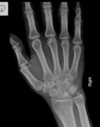

Fratura de Bennett

Fratura da base do primeiro metacarpo;

Intra-articular;

Dois fragmentos.